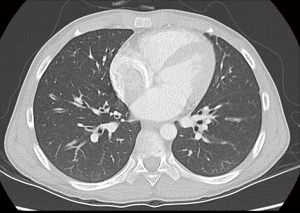

Initial laboratory findings, including complete blood count, liver function tests, CRP, amylase, and lipase, were unremarkable with a normal eosinophil count (4.3%, 450/µL). Fecal immunochemical testing was positive, and the fecal calprotectin (FC) level was 673 mg/kg. No pathogens were detected in stool culture or by multiplex polymerase chain reaction (PCR) (Seegene Inc.). Water’s view radiography demonstrated right frontal and bilateral maxillary sinusitis (Figure 1). Plain chest radiography demonstrated suspicious bronchiectatic lesions in both lung fields (Figure 2). Chest computed tomography (CT) demonstrated subsegmental atelectasis in the right middle lung field and diffuse bronchiectasis in both lungs (Figure 3). Abdominal CT and magnetic resonance (MR) enterography showed diffuse wall thickening from the distal ileum to the ascending colon. Pancreatic atrophy with diffuse calcification was observed with peripancreatic fat infiltration indicated chronic inflammation (Figure 4).